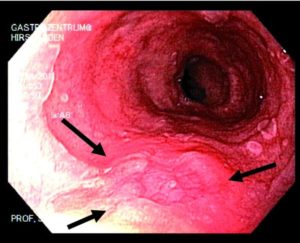

На фото слизистая глотки после химического ожога кислотами

- Первая степень – ожог поверхностный, общей реакции организма нет. Повреждение тканей выглядит как неравномерные белые и красные отечные участки слизистой оболочки гортани. Через 2-3 дня после травмы они начинают отторгаться, обнажая поврежденную розовато-красную слизистую, которая затем затягивается здоровыми клетками.

- Вторая степень – более глубокое повреждение, характеризующееся поражением не только слизистого, но и подслизистого слоев. При осмотре ожог выглядит как покраснение и отек стенки гортани с участками отторжения слизистой, бело-серым налетом и волдырями.

Выражены симптомы интоксикации (лихорадка, слабость, сонливость, отсутствие аппетита). Спустя несколько дней поврежденная ткань отслаивается, обнажая эрозии и язвы. При правильном лечении спустя 1-2 неделю они заживают практически без рубцов.

- Третья степень – серьезный ожог, в ходе которого происходит некроз (отмирание) глубоких слоев стенки гортани с образованием язв и грануляций. Симптомы интоксикации выражены очень сильно, пациент нуждается в стационарном лечении. В ходе заживления эрозий часто возникают кровотечения.